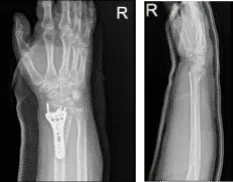

She was here with x-rays of the right wrist which showed 3 views of the right wrist in fiberglass presented for evaluation. Bony detail obscured by overlying fiberglass. Impacted distal transverse distal right radius fracture noted with slight dorsal tilt, post reduction.

Right wrist x-ray 3 or more views

Pronator quadratus was exposed and cut along the radial border with the use of Bovie. The fracture site was opened and washed thoroughly. The fracture was reduced with the help of K-wires. A volar plate was applied. The plate and fracture were found to be in an acceptable position.

The plate was fixed to the distal radius with the use of locking and nonlocking screws. The wound was thoroughly irrigated and draped. Wounds were closed in layers using #2-0 Vicryl and #4-0 Monocryl. Dressing was done using Adaptic, 4×4, and Webril. Short arm splint was applied. The patient was extubated and moved to recover in a stable condition.